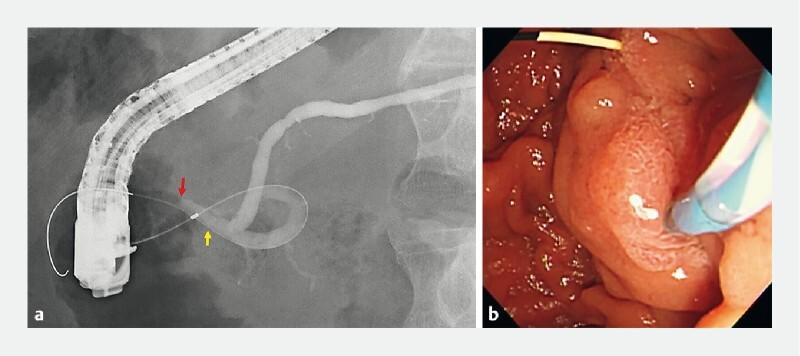

Mandai Koichiro, Shinomiya Ryo

Department of Gastroenterology, Kyoto Second Red Cross Hospital, Kyoto, Japan.

Endoscopy. 2022 Dec;54(S 02):E1051-E1052. doi: 10.1055/a-1913-7425. Epub 2022 Aug 25.